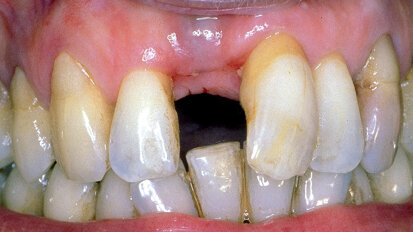

Management kosti a měkkých tkání při komplexní rekonstrukci jednoho zubu implantátem

Rekonstrukce jednoho frontálního zubu implantátem bývá pravděpodobně největší estetickou výzvou pro praktického zubního lékaře. Správné ...